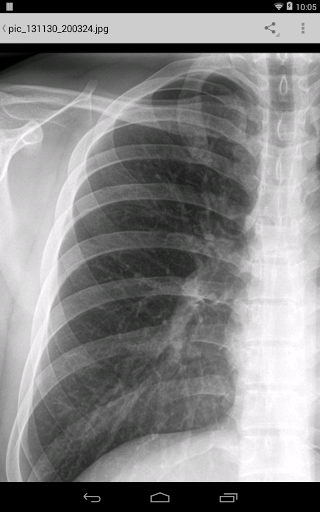

• Pendant les visites des patients, ajouter des notes de visite / médicales comme du texte, une image, un enregistrement vocal ou une écriture manuscrite